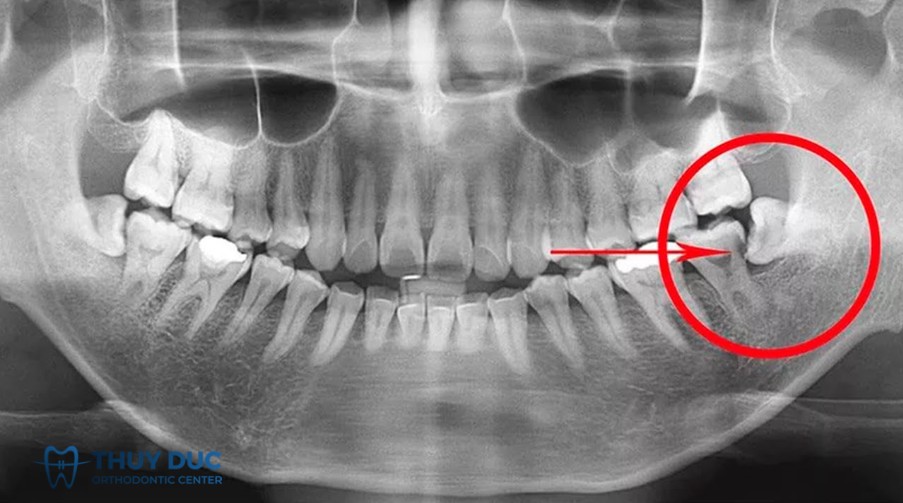

- Vị trí và hướng mọc của răng khôn: Những răng mọc lệch, nghiêng, ngầm hoặc nằm sát ống thần kinh dưới hàm hoặc sâu trong xương làm phẫu thuật khó hơn và tăng nguy cơ tổn thương dây thần kinh, chảy máu hoặc các biến chứng khác.

Vì vậy, khi có quyết định nhổ răng khôn, bệnh nhân nên tìm hiểu các phòng khám uy tín để bác sĩ đánh giá kỹ bằng phim (ví dụ CT/CBCT) để xác định mối quan hệ giữa chân răng khôn và ống thần kinh, và cân nhắc phương án giảm thiểu rủi ro (ví dụ giữ lại chân răng – coronectomy) nếu cần.